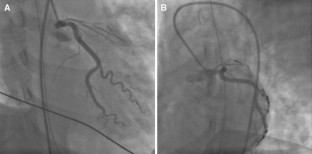

A 35-year-old woman was admitted to our hospital because of a sudden cardiac arrest caused by an acute anterior myocardial infarction. Emergency coronary angiography showed total occlusion of the proximal left anterior descending artery (LAD). We performed an intravascular ultrasound (IVUS) to detect the LAD orifice and successfully inserted the guidewire to the occluded LAD. An IVUS revealed coronary dissection and no atheromatous plaque from the orifice to the mid-portion of the LAD and the guidewire was in the true lumen. Two bare metal stents were implanted in the proximal and mid portion of the LAD. After stenting to the LAD, coronary dissection retrogradely extended to the left circumflex artery (LCx). Therefore, we performed additional stent implantation from the left main trunk (LMT) to the proximal LCx and the just proximal LAD. An IVUS guided percutaneous coronary intervention (PCI) enabled complete revascularization to spontaneous coronary artery dissection.

Fig. 4

Fig. 5